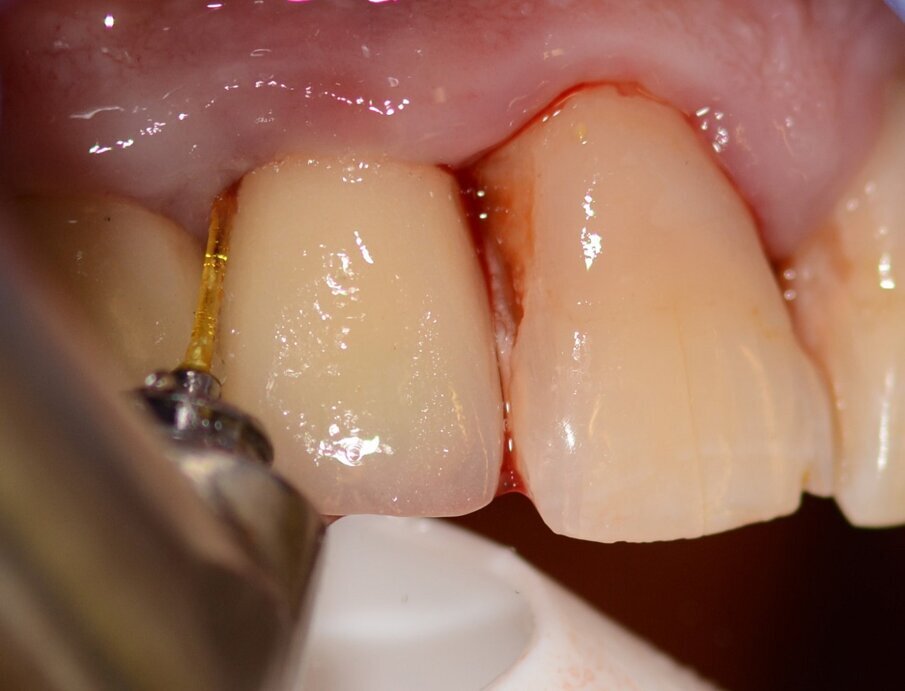

Case 1 was a patient who presented with deep pockets (9 mm), bleeding on probing and visible purulent effusion (Figs. 1–7) and was treated with a non-surgical protocol.

Fig. 1: Initial situation.

Fig. 2: Pocket depth measurements.

Fig. 3: Bleeding on probing.

Figs. 4 & 5: Use of the Er:YAG laser Varian tip for granulation tissue removal, implant surface decontamination...

...and surface ablation of infected bone.